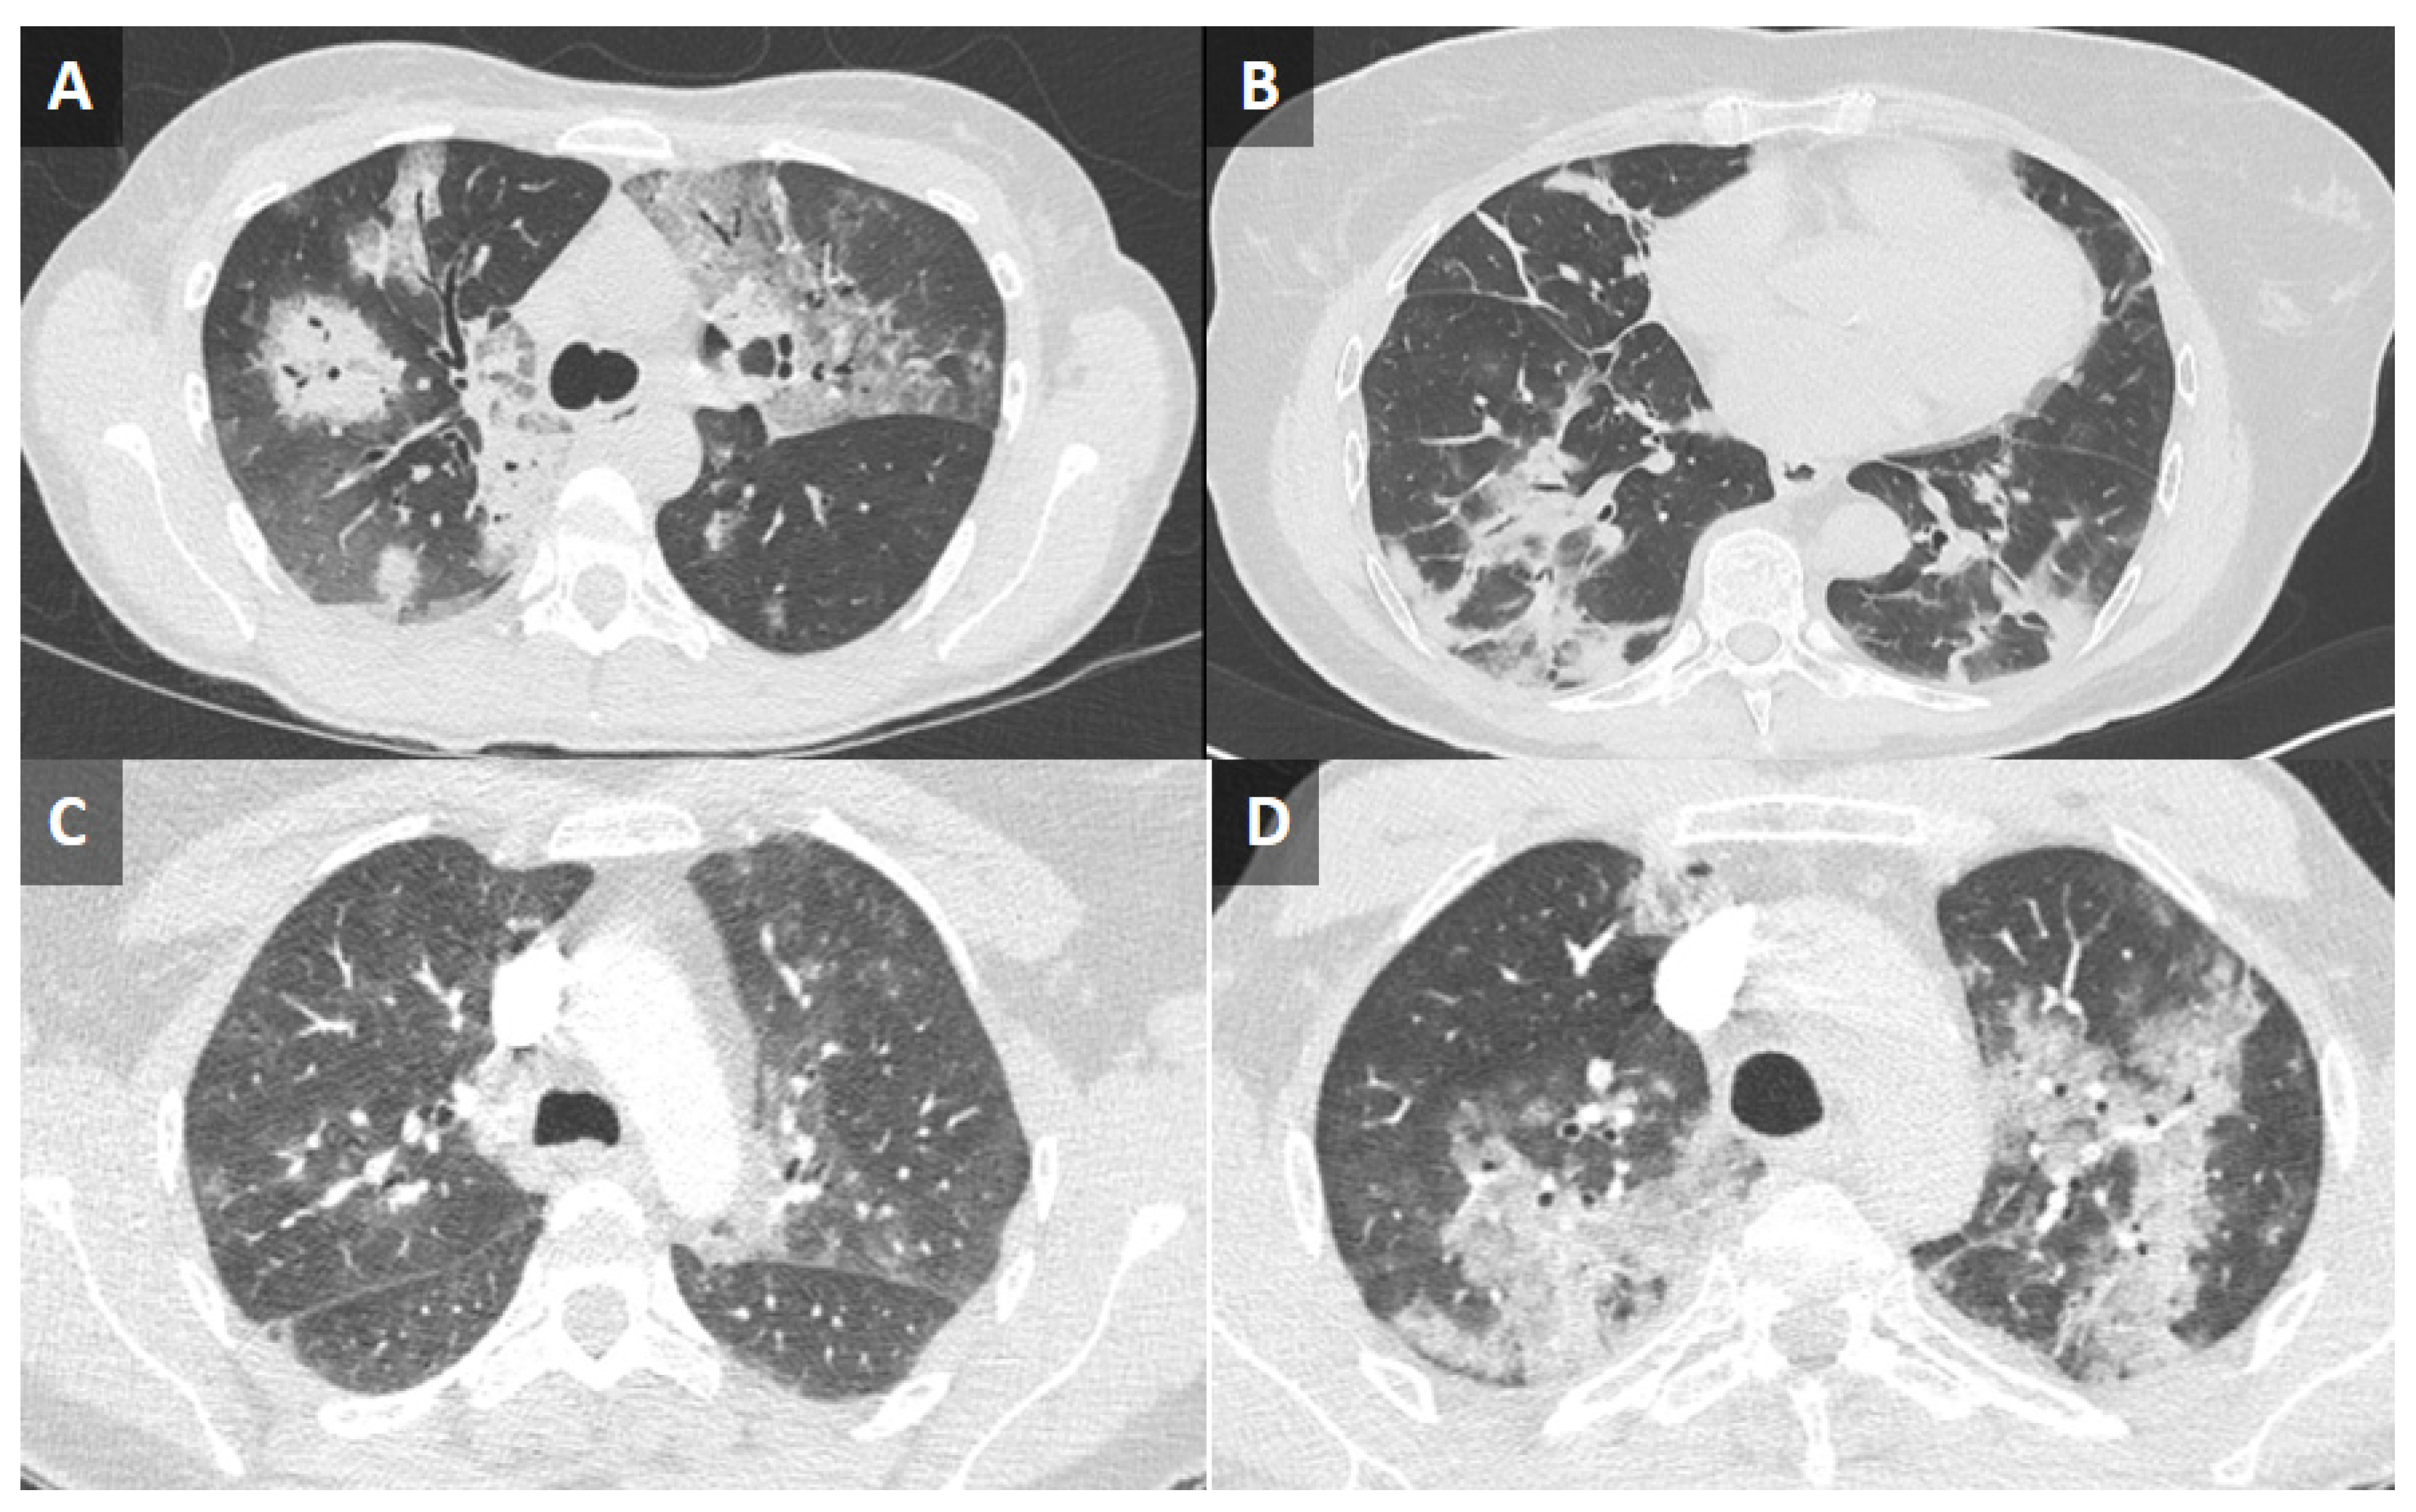

| Pulmonary CT scan | Bilateral interstitial lung disease, bilateral GGO | Bilateral GGO | Bilateral GGO with a basal distribution | Ground glass and consolidation in middle and lower lobes | |